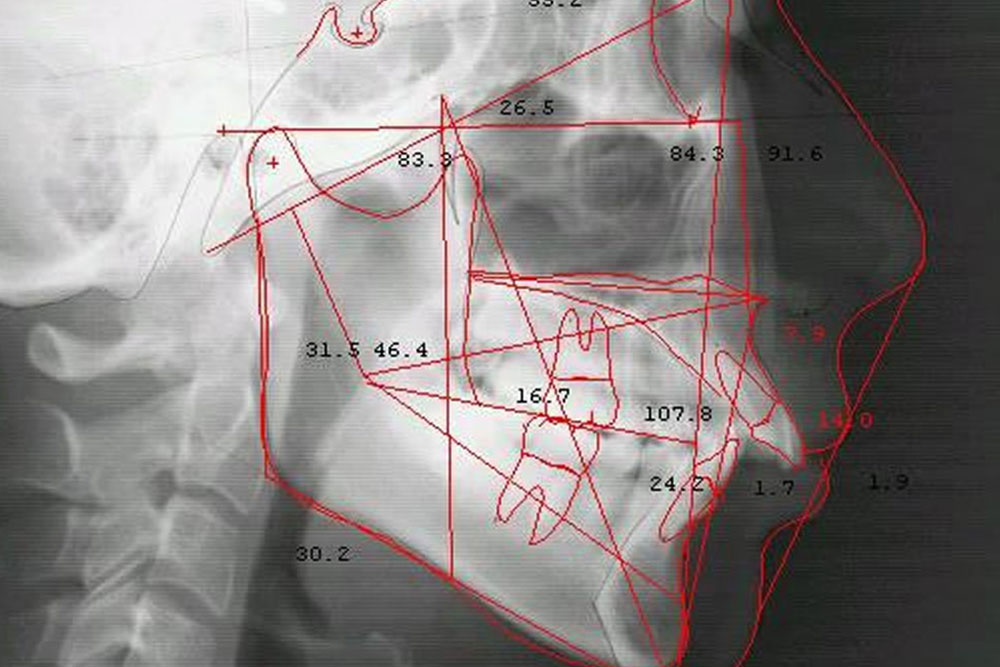

矯正治療におけるセファロレントゲンの活用

矯正治療では、歯並びの見た目だけでなく、上下の顎の位置関係や骨格全体のバランスを把握することが大切です。

そのため当院では、矯正治療の診断時に必要に応じて、セファロレントゲン(側方頭部X線規格写真)を撮影しています。

セファロレントゲンは、頭部を一定の条件下で撮影するX線写真で、歯の傾きや上下顎の前後関係、骨格の状態などを確認することができます。

これらの情報を基に、患者さま一人ひとりに適した矯正装置の選定や治療計画を立案します。

矯正治療の経過・お子様の顎の成長の確認にも活用します

セファロレントゲンは、矯正治療の開始時だけでなく、成長期のお子さまの矯正治療の際の顎の成長の様子を把握したり、治療の経過を確認する際にも使用します。

治療前後や治療途中で撮影した画像を比較することで、歯の動きや上下顎の位置関係、骨格の変化などを視覚的に確認することができます。

骨格や顎の位置関係を継続的に確認することで、治療後の歯並びが安定しやすいかどうかを検討する材料となり、しっかりと対策することによって後戻りのリスク軽減にもつながります。